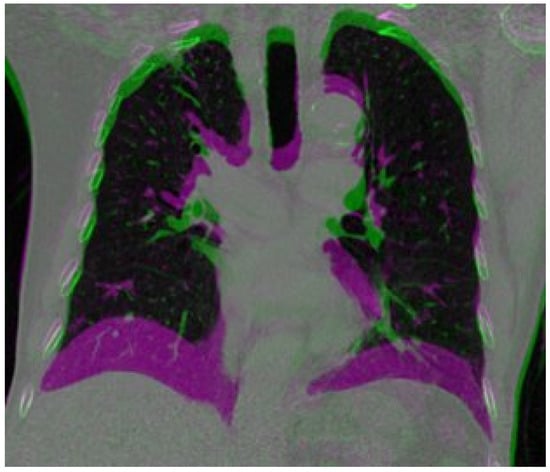

Despite the progress made in the use of deep learning techniques for deformable image registration, accurately estimating large and irregular deformations caused by respiration remains a challenging task. This is particularly important in the context of medical image registration, as tumors and sensitive structures in the thorax can move more than 20 mm [21] during respiration, making it difficult to achieve accurate registration. Figure 1 shows a large deformation in the diaphragm and near the heart area.

Figure 1. A composite image by overlaying the inspiration image onto the expiration image. The large differences are presented as magenta color.